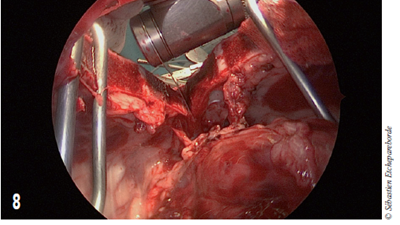

Photo 8

Une scie oscillante est utilisée pour couper le sternum en deux dans le sens de la longueur (ici vue depuis le thorax).

Bien que la masse ne soit effectivement pas invasive dans les vaisseaux sanguins, le risque de percer la capsule en manipulant la masse afin de disséquer les attaches dorsales était trop grand et la chirurgie a été convertie.

Une sternotomie a été réalisée et la dissection a été terminée au Ligasure®. Un drain thoracique a été mis en place et la sternotomie a été refermée avec du PDS placé en 8 autour des synchondroses sternales. Le drain a pu être enlevé après 72 heures.